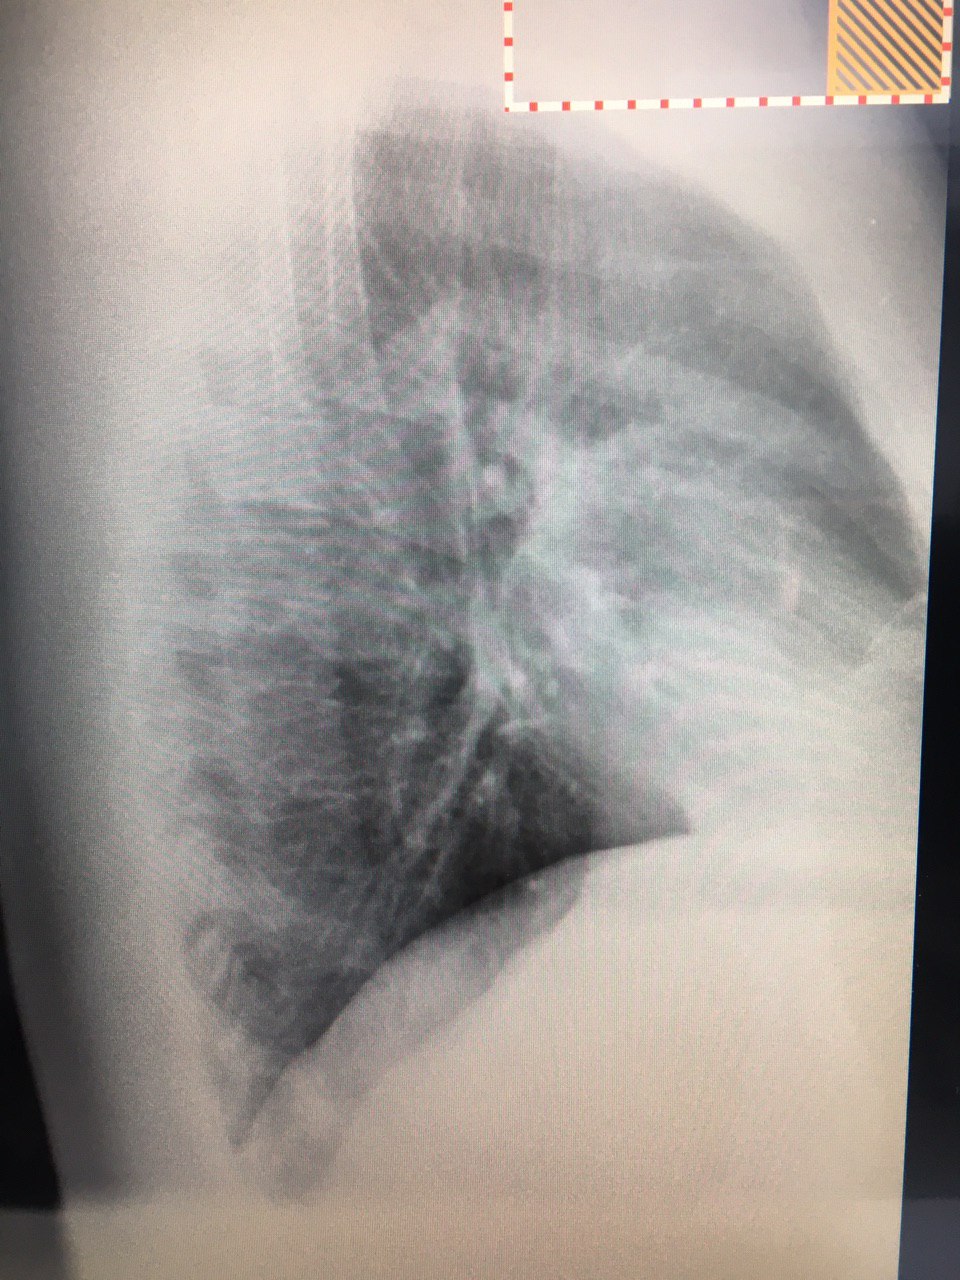

Скинула выше бок

Скинула выше бок

Ладно. Хотел в позитиве бок глянуть

Позитив)

Что-то есть ☺️😏